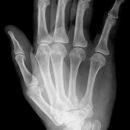

Hand d.v. (dorso-volar)

Indikation

Frakturen, entzündliche (Arthrose) und degenerative Veränderungen (Arthritis), chronische Polyarthritis (Rheuma)

Lagerung

Patient sitzt seitlich zum Tisch, Beine befinden sich neben Tisch abgewinkelter Unterarm und die Handfläche liegen auf.

Zentralstrahl

senkrecht auf Objektmitte

Einblendung

proximal einschließlich Proc. styloideus radii und ulnae

Anmerkung

Übersichtsdarstellung des Skeletts bei Frakturen, Arthrosis und Deformierung der Gelenke, sowie chronischer Polyarthritis (Rheuma).

Fragestellungsabhängige Einblendung mögl. z. B. Mittelhand

Qualitätskriterien

vollständige Darstellung der ganzen Hand inklusive Handgelenk, Buchstabe